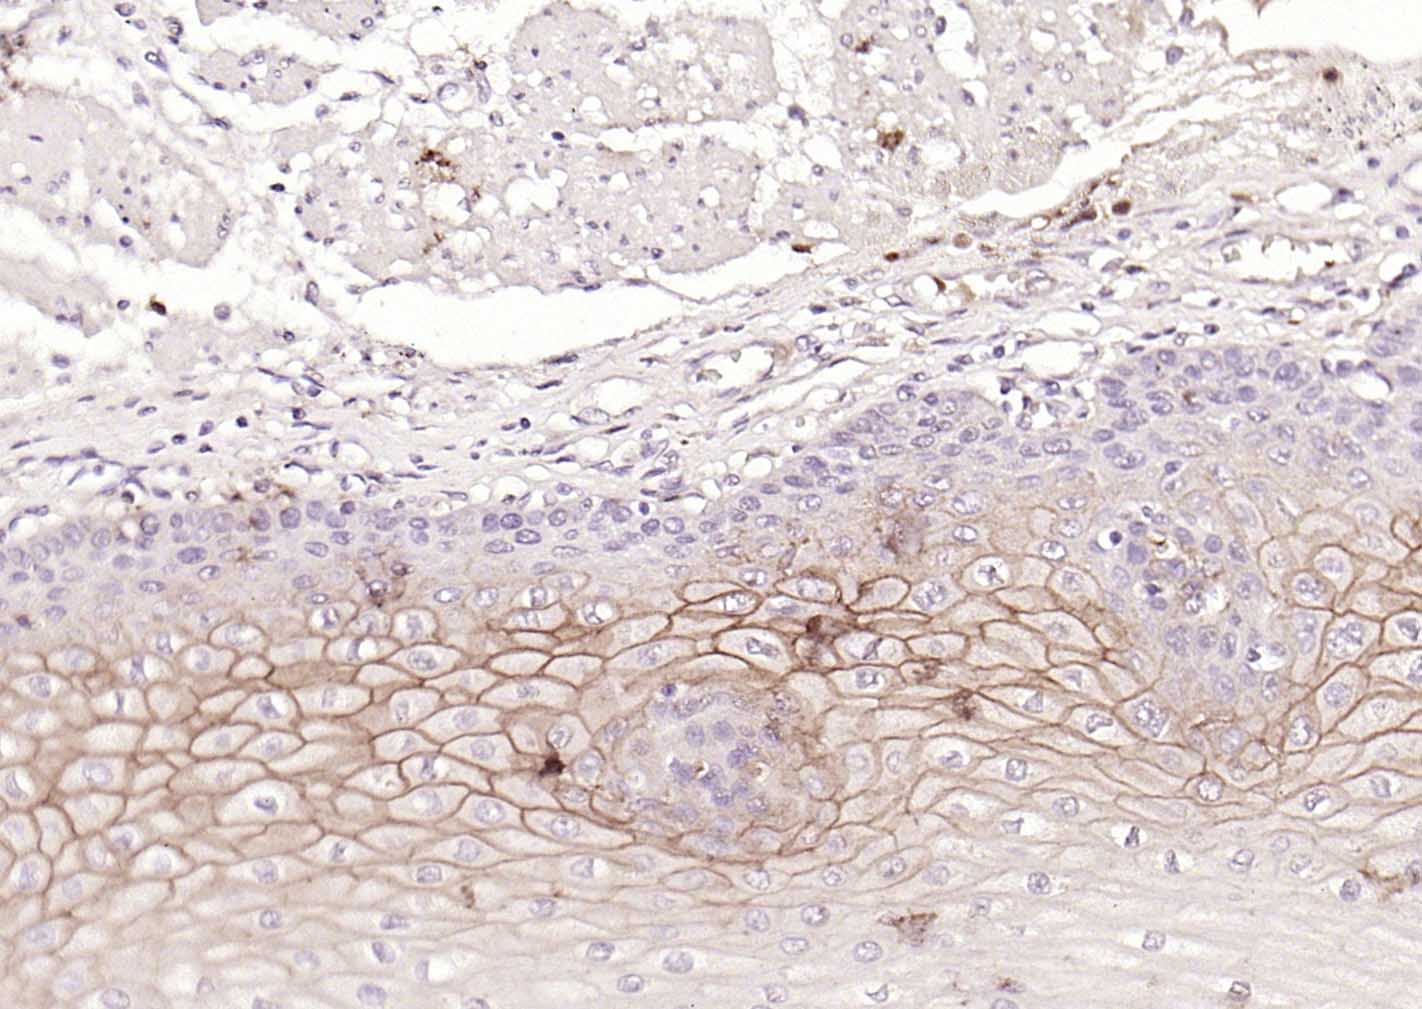

Paraformaldehyde-fixed, paraffin embedded (human cervical carcinoma); Antigen retrieval by boiling in sodium citrate buffer (pH6.0) for 15min; Block endogenous peroxidase by 3% hydrogen peroxide for 20 minutes; Blocking buffer (normal goat serum) at 37°C for 30min; Incubation with (CD138) Monoclonal Antibody, Unconjugated (bsm-60902R) at 1:200 overnight at 4°C, followed by operating according to SP Kit(Rabbit) (sp-0023)instructionsand DAB staining.

Paraformaldehyde-fixed, paraffin embedded (human esophagus); Antigen retrieval by boiling in sodium citrate buffer (pH6.0) for 15min; Block endogenous peroxidase by 3% hydrogen peroxide for 20 minutes; Blocking buffer (normal goat serum) at 37°C for 30min; Incubation with (CD138) Monoclonal Antibody, Unconjugated (bsm-60902R) at 1:200 overnight at 4°C, followed by operating according to SP Kit(Rabbit) (sp-0023) instructionsand DAB staining.